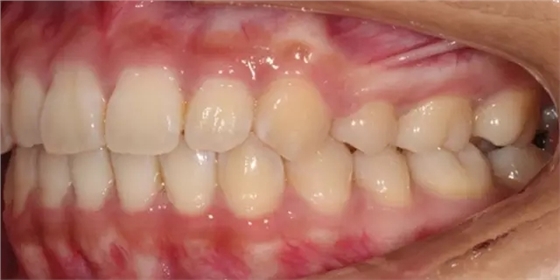

Damon 病例分享:安氏 II 類二分類露齦笑的矯治(董一磊)

上下牙列擁擠,磨牙尖牙Ⅱ 類關(guān)系,3 度的深覆牙合,上頜中切牙伸長內(nèi)傾拔除上頜雙側(cè)的第一前磨牙,先粘上頜高轉(zhuǎn)矩的自鎖托槽排齊牙列,唇向開展上頜切牙,有一定的覆蓋,粘下頜標準轉(zhuǎn)矩托槽,上頜 1, 2 之間植入種植支抗壓入,同時后牙 5, 6 之間植入種植支抗內(nèi)收前牙,打開咬合關(guān)閉間隙。治療關(guān)鍵:前牙轉(zhuǎn)矩的控制第 1 個月 上頜粘上 Damon Q 高轉(zhuǎn)矩托槽,上 .014 熱激活 NiTi 絲。第 3 個月 上換 .014 x .025 熱激活 NiTi 絲。第 5 個月 上頜基本排齊,覆蓋增大,上換 .017 x .025 NiTi絲,下頜粘托槽,下 .014 熱激活 NiTi 絲。第 7 個月 上 .017 x .025 NiTi 絲加搖椅,下?lián)Q .014 x .025 熱激活 NiTi 絲第 9 個月 上頜換 .019 x .025 NiTi 絲加搖椅,下頜換 .017 x .025 NiTi 絲第 11 個月 下頜換 .019 x .025 加搖椅,上頜 1, 2 之間, 5, 6 之間植入種植釘,下頜出現(xiàn)散隙。第 13 個月 上頜換 .019 x .025ss 加搖椅,前牙種植釘用 Power Chain 壓低前牙(每側(cè) 100g),后牙種植釘關(guān)閉間隙(每側(cè) 150g),下?lián)Q .019 x .025ss,Power Chain 關(guān)閉間隙。第 19 個月 上頜前牙基本壓低到位去除前牙種植釘,繼續(xù)用關(guān)閉間隙,下頜散隙關(guān)閉。

第 22 個月 上頜覆蓋變小,去除 5, 6 之間種植釘,后牙前移關(guān)閉間隙。第 30 個月 患者未配合中線牽引,下中線仍有 1mm 右偏,患者對矯治效果滿意要求拆除,拆除固定矯治器,取模制作壓模保持器。 1.骨性 Ⅱ 類的患者內(nèi)收前牙時需對上頜前牙的轉(zhuǎn)矩進行較好的控制才能獲得良好的面型和唇部形態(tài)。 2.露齦笑的患者治療前要分析其病因是唇、牙齦、牙齒、牙槽骨、上頜骨或多種因素結(jié)合,再制定矯治方案。 3.Ⅱ 類第二分類伴露齦笑的患者的上頜前牙移動軌跡是唇向開展-壓低-整體內(nèi)收。 4.Ⅱ 類第二分類牙齒舌傾比較厲害的情況,上頜中切牙慎用樹脂咬合墊。 5.壓低前牙或控根移動時容易發(fā)生牙根的吸收,需輕力緩慢的移動。